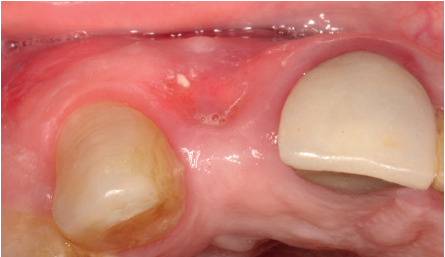

Se presenta el caso de una mujer de 36 años que acude a la consulta demandando solución para un implante situado en la posición 1.2. Este implante ha llevado una rehabilitación con una corona durante un corto período de tiempo en el que se produjo una mucositis importante y una pérdida del grosor del tejido gingival, por lo que la corona fue retirada.

La paciente presenta un provisional removible y el tejido blando circundante a la zona de la emergencia inicial de la prótesis implantosoportada se encuentra en malas condiciones, con una pérdida de grosor importante y los restos de una fístula de tejido blando (Figuras 1-4).